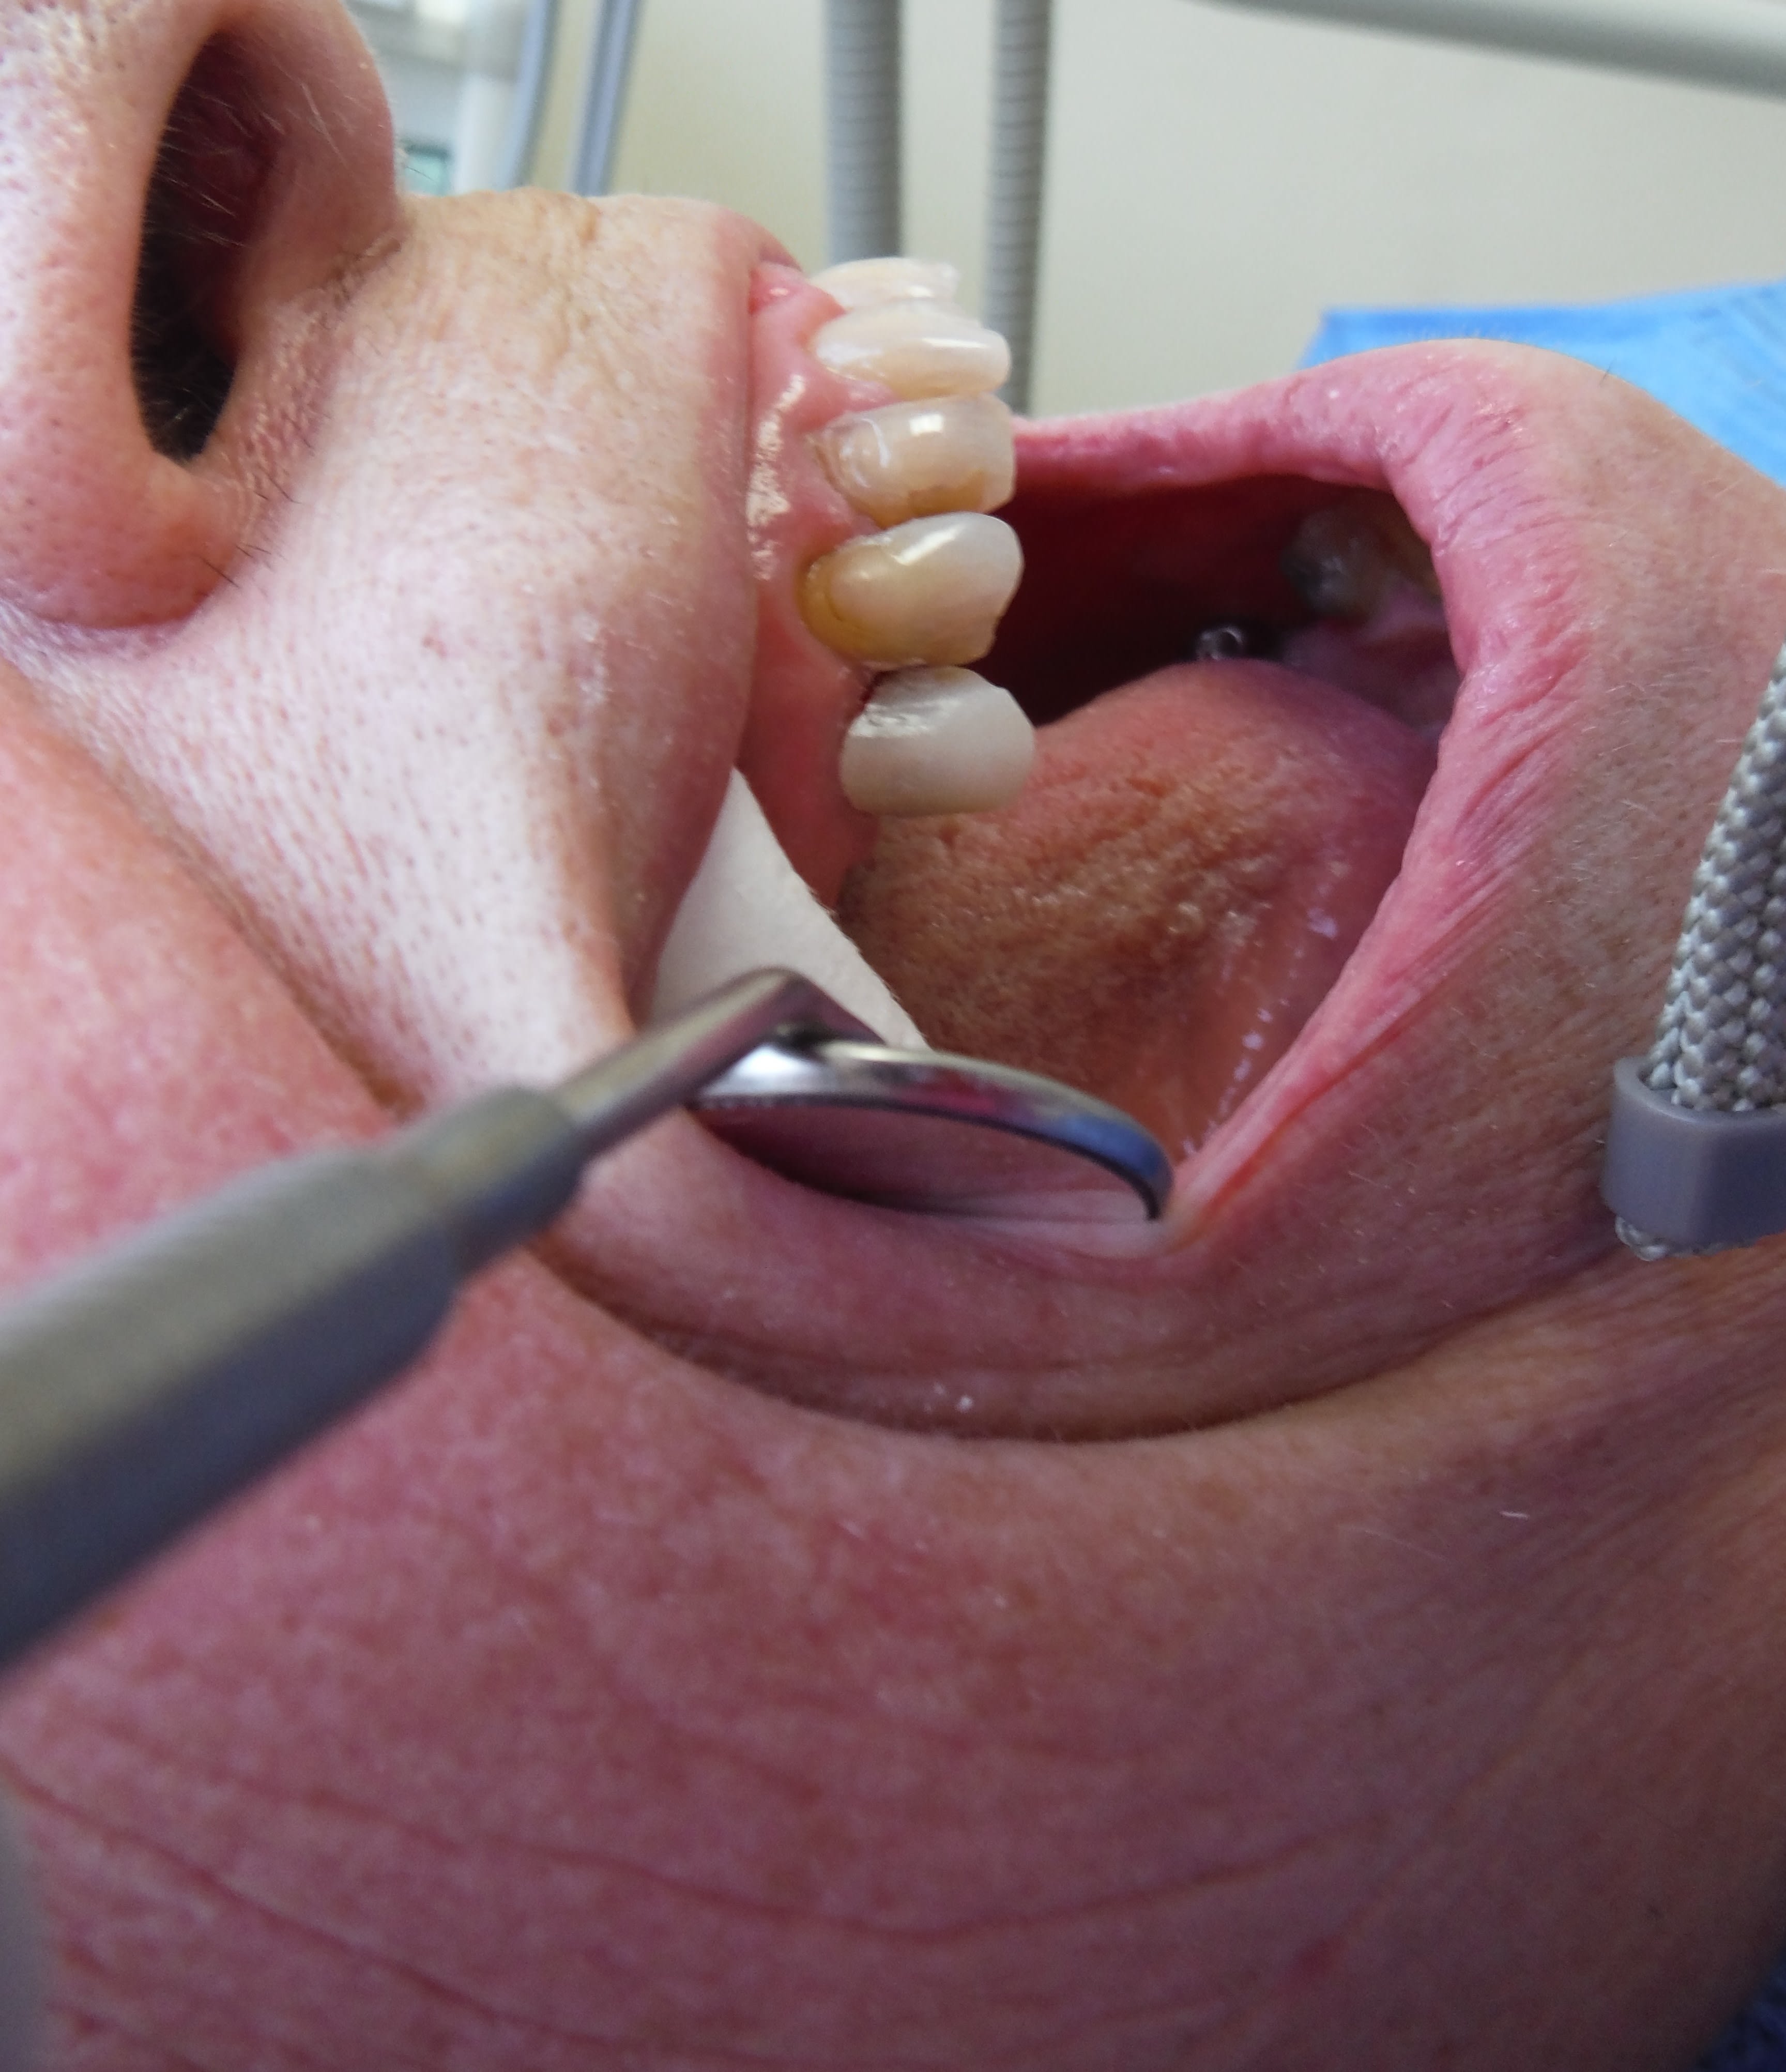

Tiens regarde, la photo est bof bof.

Il manque la 24, la 23 est très usée, pour moi non reconstituable durablement mais pas à dévit, donc indication de CR et voilà mon pilier antr, la 25 sera aussi pilier sur dent vivante.

Là j’appâte le "enlaye", ça devrait mordre ;-))

Je pense que le contexte occlusal a aggravé les abrasions, abfractions, ce qui contre-indique les facettes et fera décoller les compos, non crois moi, une CR est souhaitable!-)

Et un implant, si il le pilonne pareil... la prothèse morte... il y aura de la casse, à mon avis sur les 23 et 25 (une petite pièce sur la 25 "ho! Vous n'avez pas de chance! A peine fini, celle d'à coté qui casse... vraiment c'est pas de chance! Bon, bah implant!-))

Si Enlaye était là, il te le dirait, la ferraille en bas à droite est pas équilibrée, sous-occ ou interférence, et le patient surcharge ses 21 22 23, si compos cela décollera, et si facettes, alors là c'est Noël, bonjour le SAV!